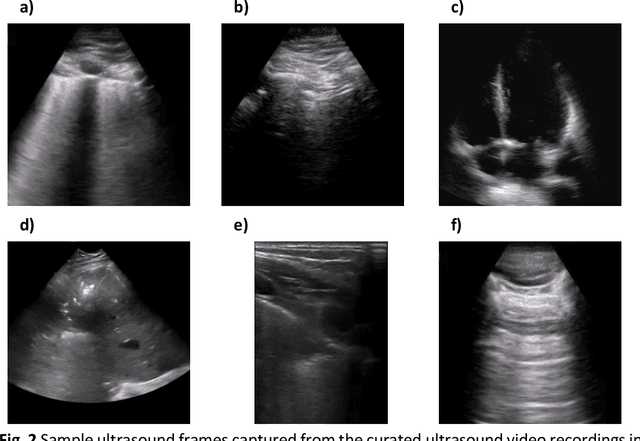

Abstract:The COVID-19 pandemic continues to have a devastating effect on the health and well-being of the global population. Apart from the global health crises, the pandemic has also caused significant economic and financial difficulties and socio-physiological implications. Effective screening, triage, treatment planning, and prognostication of outcome plays a key role in controlling the pandemic. Recent studies have highlighted the role of point-of-care ultrasound imaging for COVID-19 screening and prognosis, particularly given that it is non-invasive, globally available, and easy-to-sanitize. Motivated by these attributes and the promise of artificial intelligence tools to aid clinicians, we introduce COVIDx-US, an open-access benchmark dataset of COVID-19 related ultrasound imaging data that is the largest of its kind. The COVIDx-US dataset was curated from multiple sources and consists of 93 lung ultrasound videos and 10,774 processed images of patients infected with SARS-CoV-2 pneumonia, non-SARS-CoV-2 pneumonia, as well as healthy control cases. The dataset was systematically processed and validated specifically for the purpose of building and evaluating artificial intelligence algorithms and models.